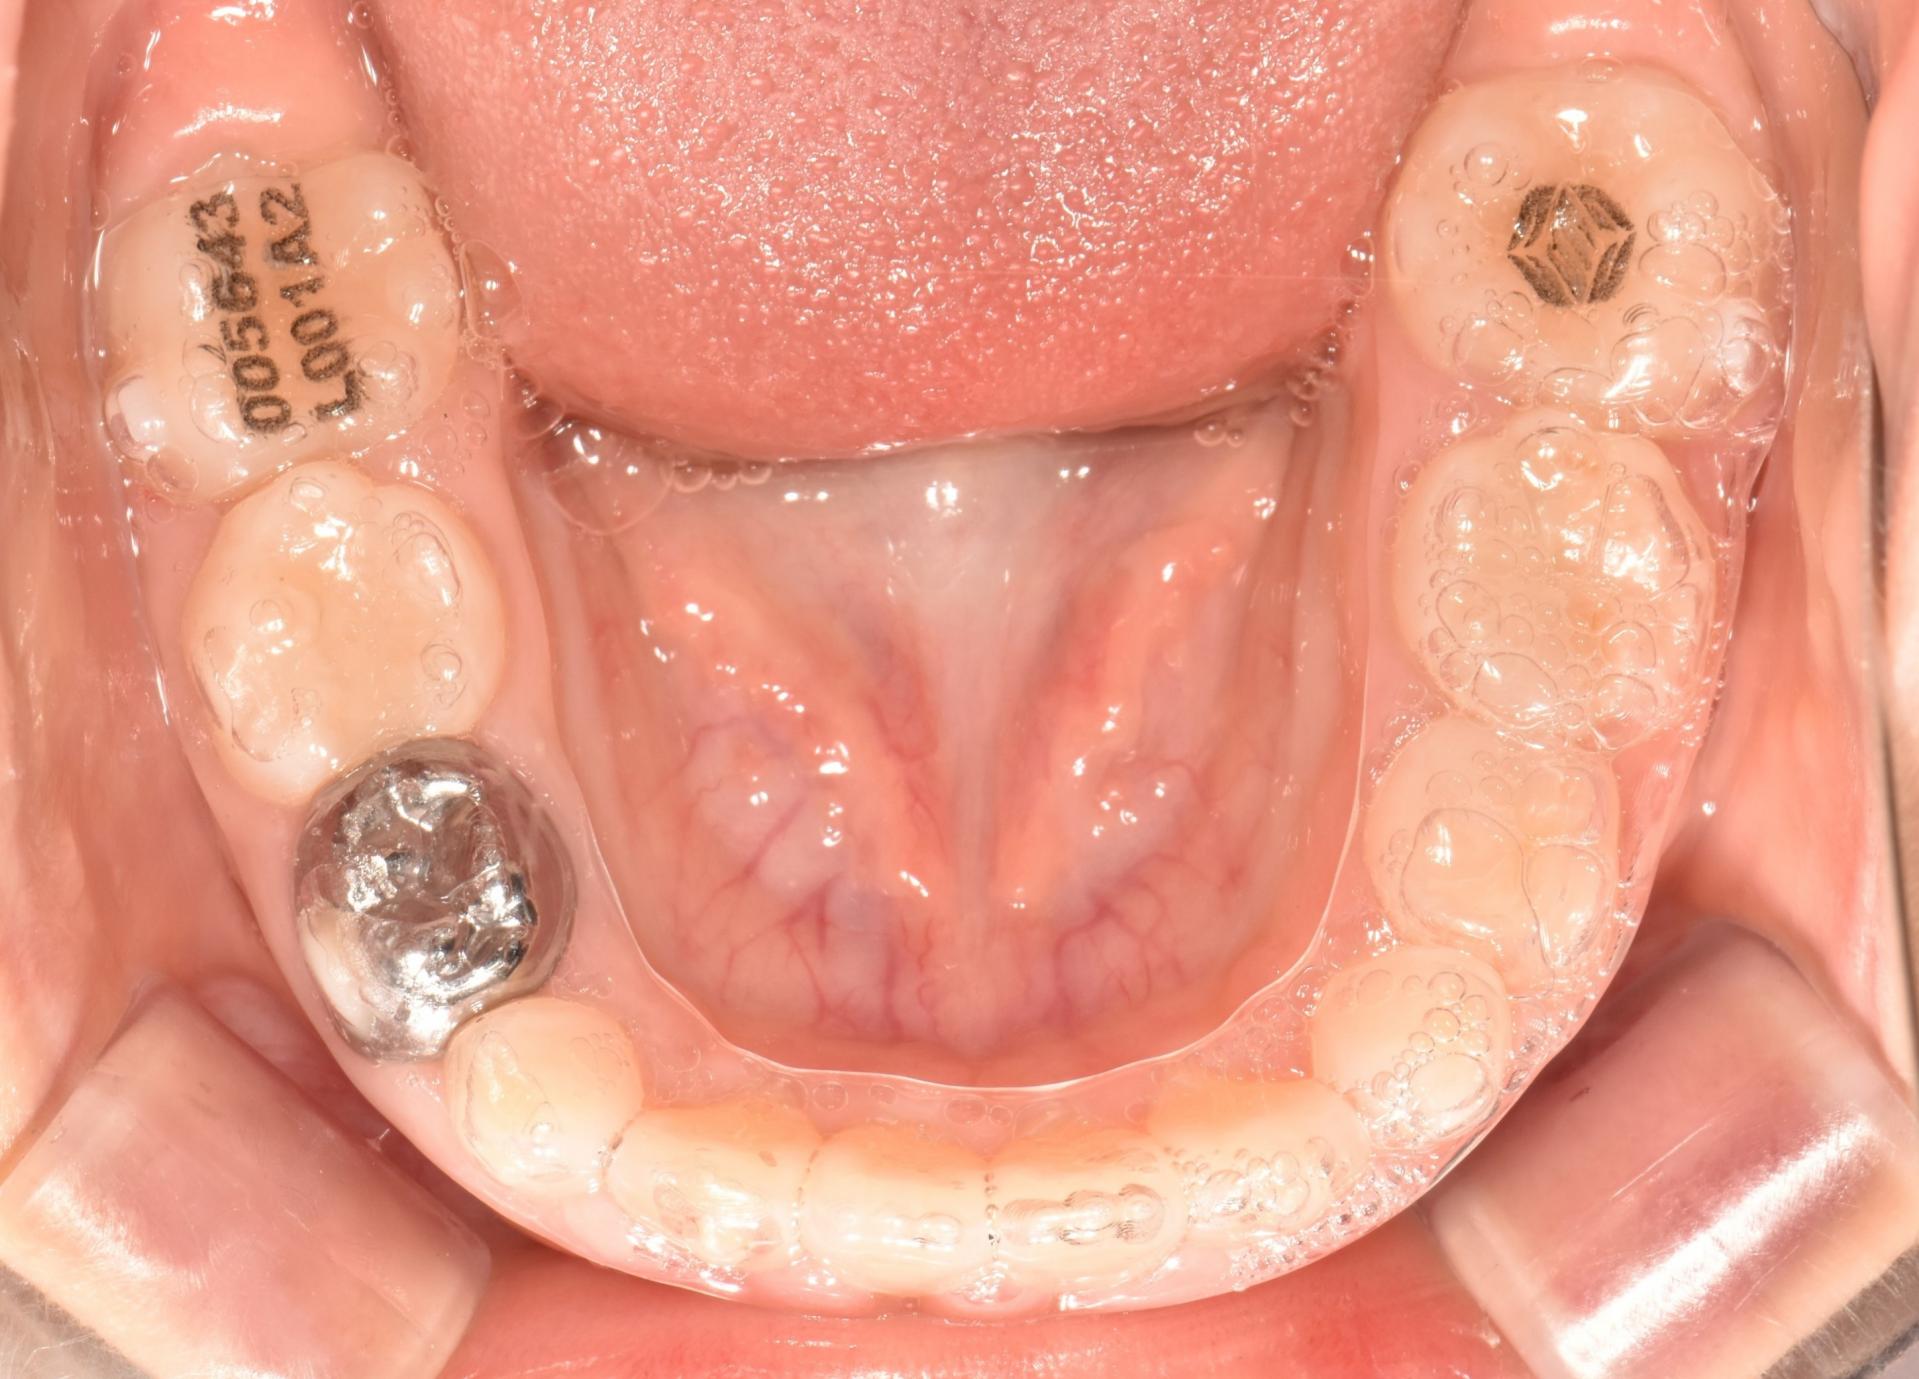

투명교정장치 착용중. 장치를 착용하여도 티가 나지 않습니다. 아이는 정말 성실하게 장치를 잘 껴주었습니다.